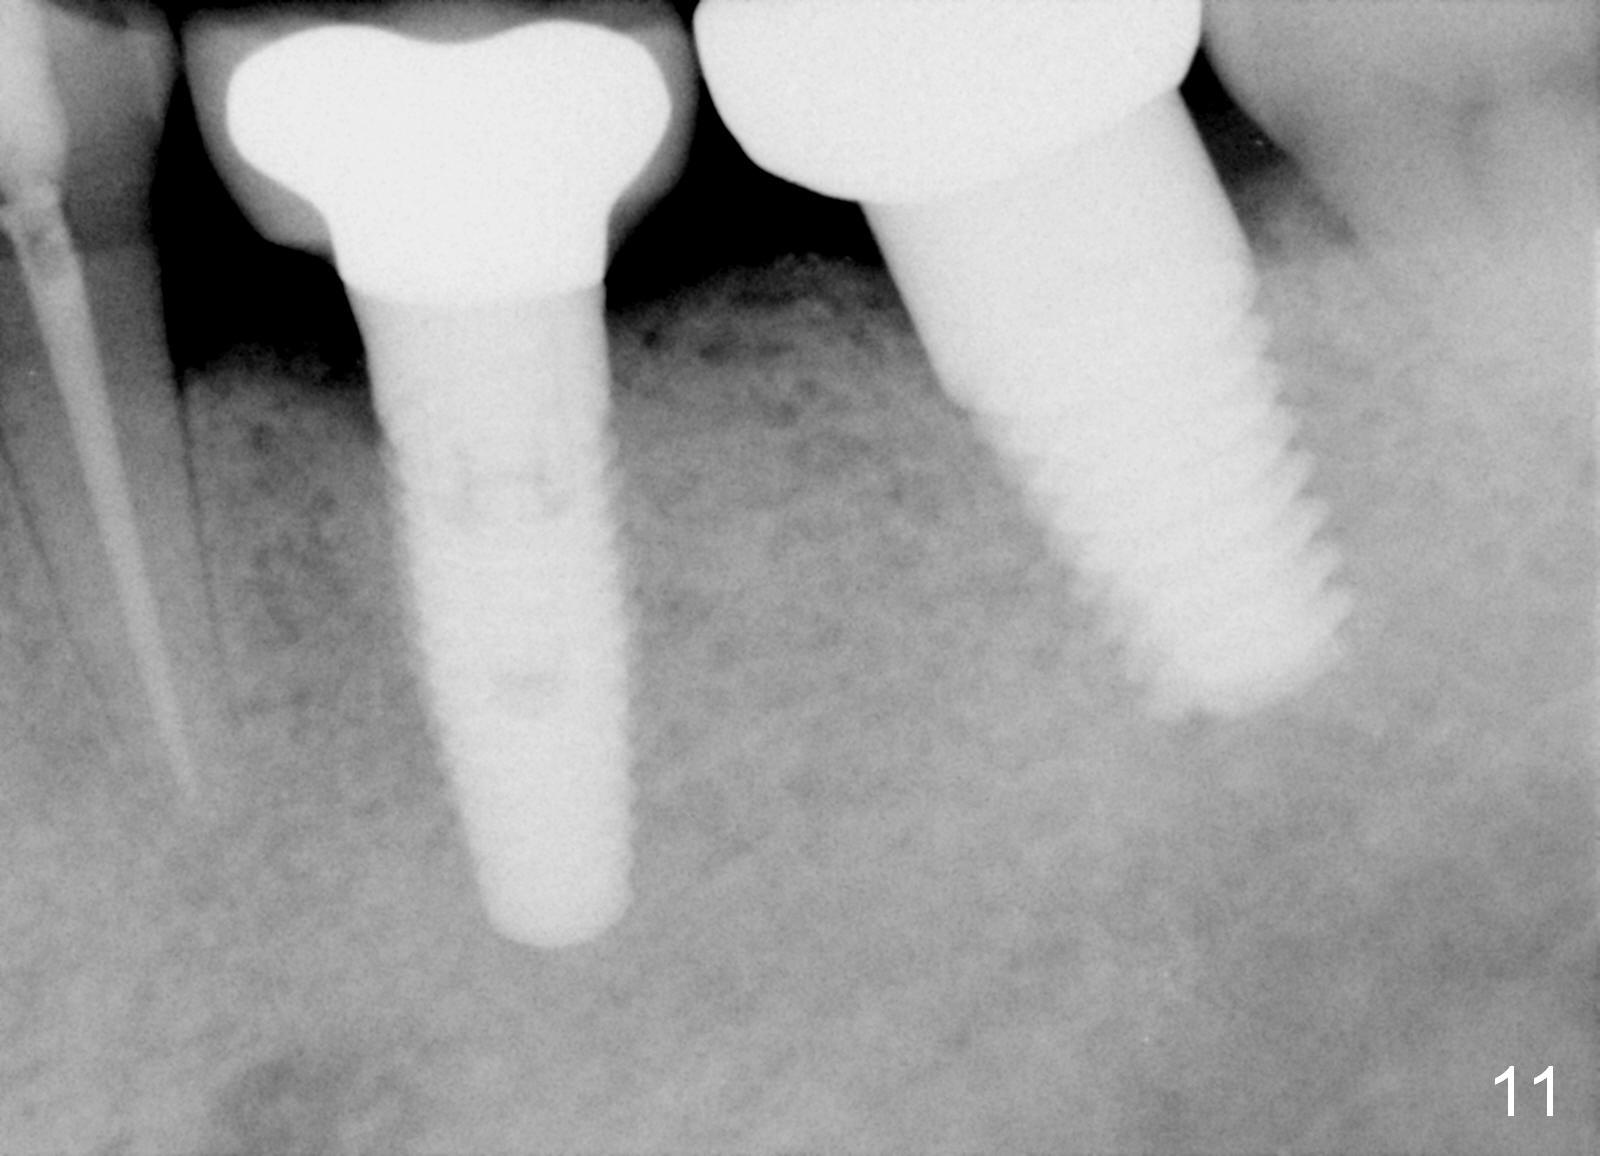

The septum of the socket is thin (Fig.3*), and easily removed, leaving a large socket. Osteotomy is initiated with 2 mm pilot drill in the middle of the socket, slightly mesiolingual, since the buccal and distal bone is low and defective. Reamers (2.5 to 4 mm in diameter) are sequentially used to enlarge osteotomy and harvest autogenous bone (Fig.4 (3 mm reamer in place). When 5 mm tap is placed, there is no stability. Six mm tap gains some stability, but the socket is not closed. Seven mm tap achieves strong stability and is closing the socket (Fig.5). Ultimately a 7x14 mm implant is placed with insertion torque more than 60 Ncm (Fig.6). The implant almost obliterates the socket (Fig.7). The harvested autogenous bone is placed in the buccal and distal aspects of the socket before Chromic gut suture (4-0) is placed distally. Fig.8,9 show the healing socket 6 days and 1.5 months postop, respectively. Osteointegration appears to occur in 2.5 months (Fig.10, compare to Fig.6). Bone level remains the same 1 year post cementation (Fig.11).

In brief, a large implant is placed in a single socket of the lower 2nd molar for primary stability and better restoration. To place an immediate implant in the middle of a lower molar socket requires knowledge of local anatomy. His bone density is high, which also helps implant placement at healed sites.